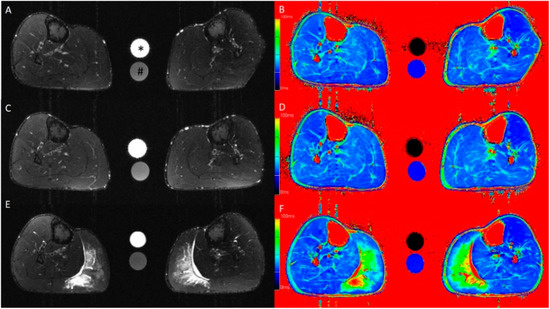

| T2 signal intensity | 30.5 ± 10.2 | 36.7 ± 14.5 | 76.2 ± 49.3 | 1.00 | 0.011 | 28.5 ± 13.1 | 32.4 ± 13.4 | 83.1 ± 70.2 | 1.00 | 0.005 | 1.00 | 1.00 | 1.00 |

| T2 relaxation time (ms) | 36.3 ± 3.3 | 39.1 ± 5.8 | 54.9 ± 23.8 | 1.00 | 0.007 | 36.3 ± 3.9 | 38.4 ± 5.5 | 57.7 ± 27.9 | 1.00 | <0.001 | 1.00 | 1.00 | 1.00 |

| Volume of edema (mL) | 12.1 ± 8.9 | 17.8 ± 11.0 | 106.4 ± 108.9 | 1.00 | 0.003 | 15.4 ± 13.0 | 18.3 ± 20.9 | 117.9 ± 135.0 | 1.00 | 0.025 | 1.00 | 1.00 | 1.00 |